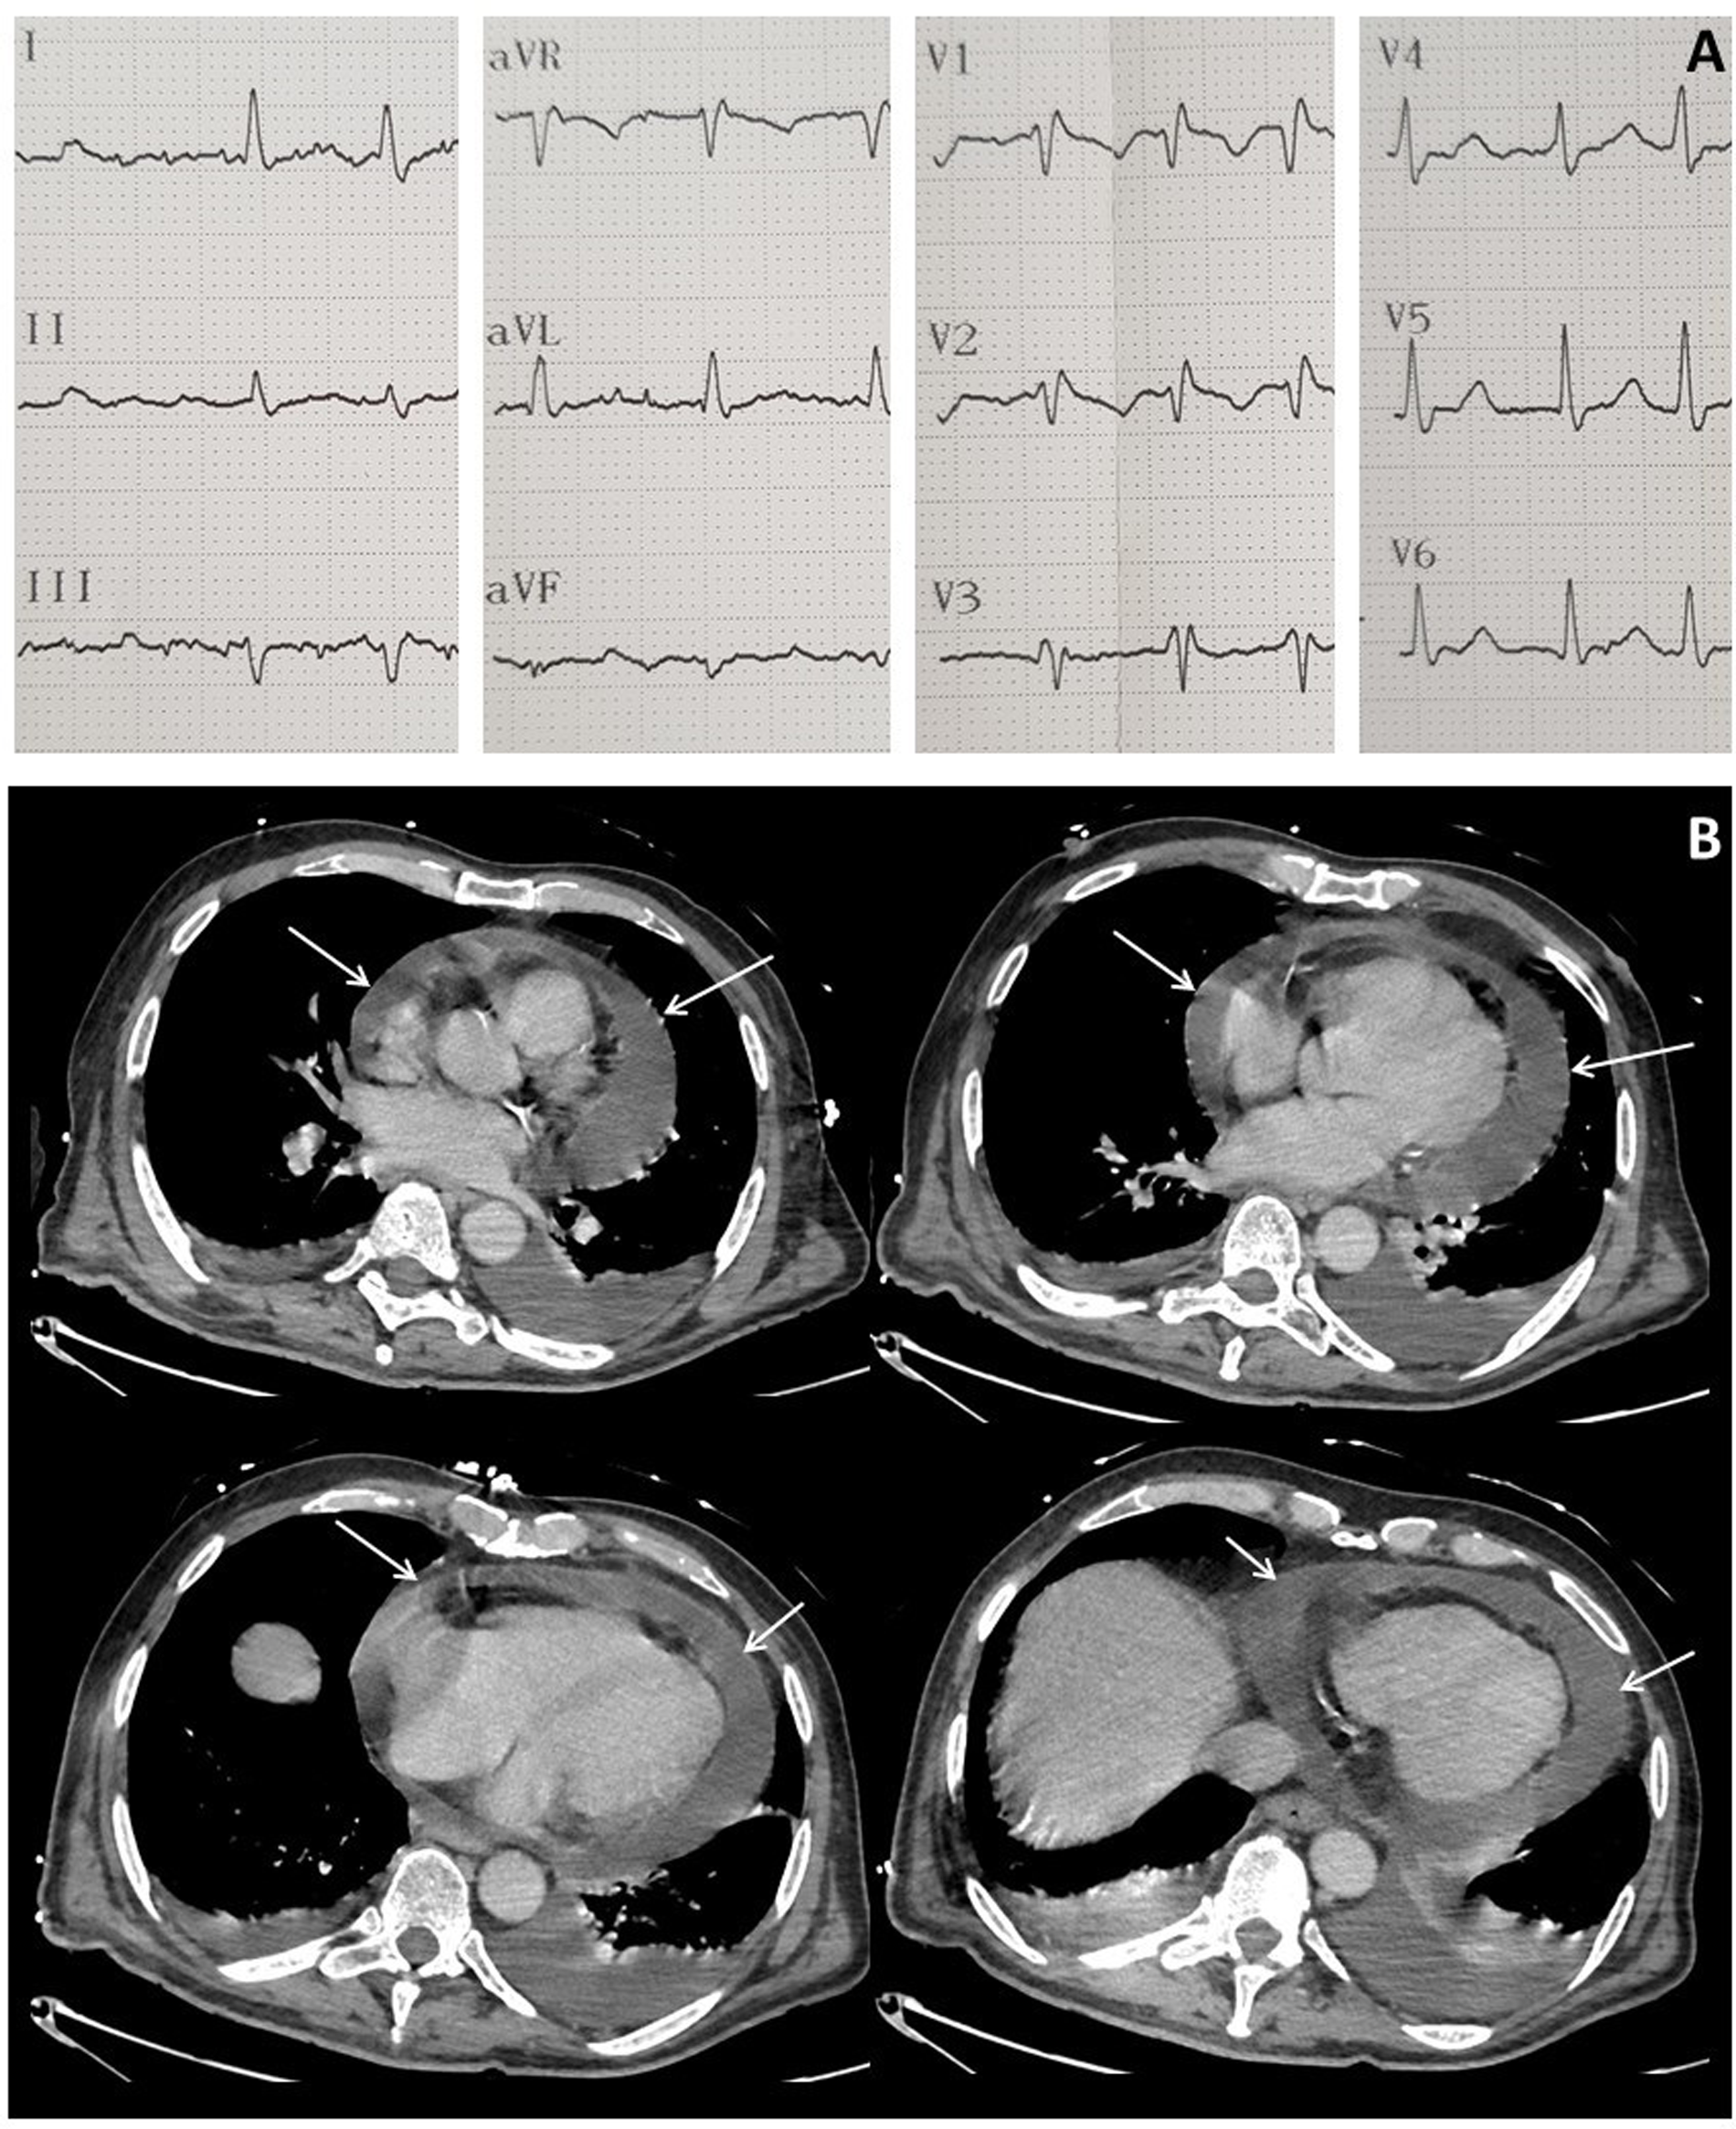

At admission to ICU, his blood pressure was 109/80 mmHg, heart rate was 118 beats/min, body temperature was 36.1°C, respiratory rate was 35 cycles/min and percutaneous oxygen saturation (SpO2) was 95% in air. The time course of the vital signs and medications following ICU admission is shown in Figure 2B. Edema of the lower limbs was observed, but no other sign of right ventricular dysfunction was noted. Heart sounds were decreased but no pericardial friction was heard. Serum C-reactive protein (CRP) was moderately elevated to 15 mg/L (normal range: ≤5 mg/L) as well as N-Terminal pro-Brain Natriuretic Peptide (3171 ng/L; normal range: ≤376 ng/L) but serum troponin T was normal (13 ng/L; normal range: ≤14 ng/L). An ECG showed atrial fibrillation, right bundle branch block but no sign of pericarditis (Figure 3A).

Figure 3

Electrocardiogram at ICU admission showing atrial fibrillation and right bundle branch block (A) and computed tomography performed after CAR-T cell therapy showing major circumferential pericardial effusion (arrows) (B).

In a context of severe thrombocytopenia (26,000/µL), brain and chest CT-scans were performed to investigate the sudden delirium and to monitor the aortic cross hematoma. No intracranial or thoracic bleeding was detected, but an increase in pericardial effusion was noted (Figure 3B).